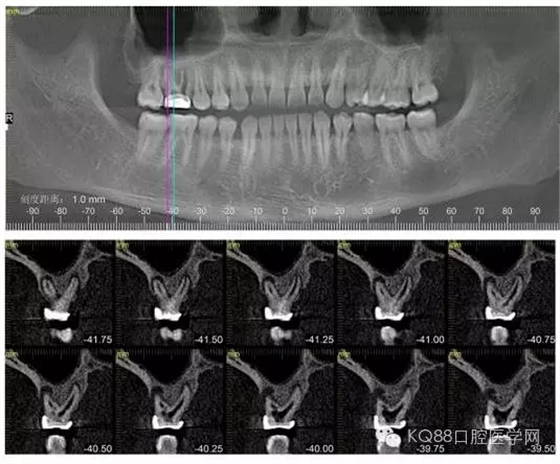

下面是拔牙前 CBCT

清晰可見根尖部陰影區(qū)域明顯。遠(yuǎn)中頰根

近中頰跟,同時(shí)可以看出離上頜竇比較近,且伴有骨缺損。

這個(gè)切面可以看到根裂。